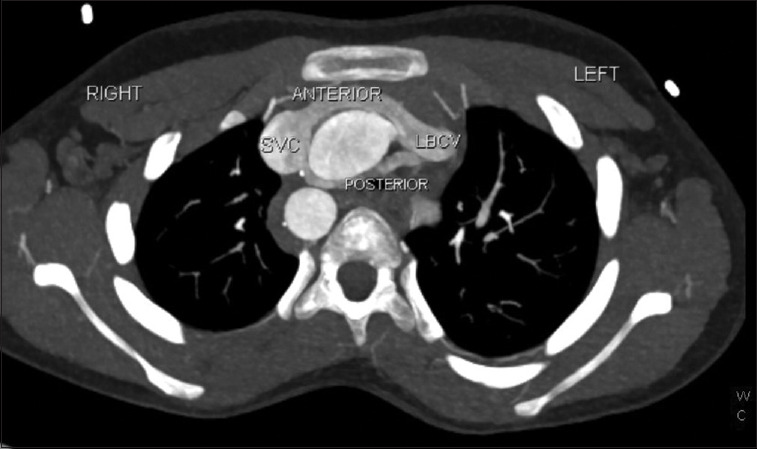

The left brachiocephalic vein (LBCV) usually passes superior and anterior to the aortic arch. In rare cases, this vein follows an anomalous course. We present a case of duplicated circumaortic LBCV in a 10-year-old child with Tetralogy of Fallot.